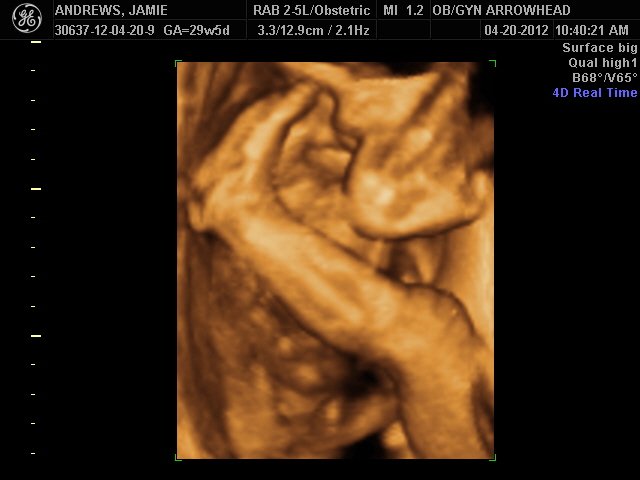

We offer complimentary 3D/4D Ultrasounds to all our OB patients around 30 weeks! The following photos are some examples of our work, shown with permission from our patients.